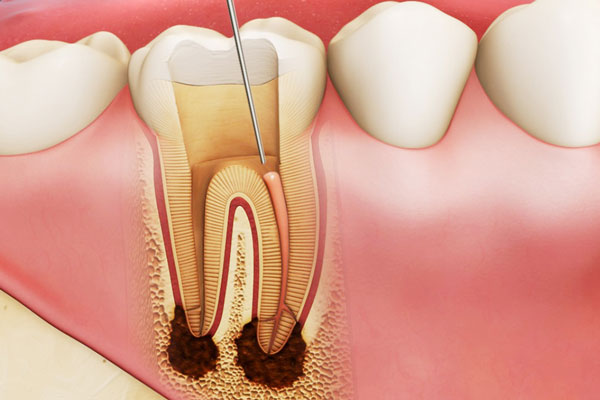

Trong đó, kỹ thuật chải răng Bass cải tiến là bước đầu tiên và quan trọng nhất. Phương pháp này cho phép lông bàn chải tiếp cận sâu vào rãnh lợi – nơi vi khuẩn thường tích tụ – bằng cách đặt bàn chải nghiêng 45 độ về phía nướu, rung nhẹ tại chỗ, sau đó quét từ lợi ra răng. Đặc biệt, bạn nên sử dụng bàn chải lông mềm, đầu nhỏ và chải răng hai lần mỗi ngày, mỗi lần ít nhất 2 phút.

Tuy nhiên, chải răng đúng cách vẫn chưa đủ. Kẽ răng là khu vực bàn chải khó tiếp cận và cũng là nơi mảng bám dễ hình thành cao răng. Chỉ nha khoa hoặc tăm nước là giải pháp bổ trợ không thể thiếu, đặc biệt quan trọng đối với những người đang mắc viêm nha chu.

Dù bạn vệ sinh tốt đến đâu, mảng bám vẫn có thể chuyển hóa thành cao răng chỉ sau 24 giờ nếu không được loại bỏ kỹ lưỡng. Khi đó, bàn chải không còn tác dụng. Cao răng là ổ vi khuẩn cứng đầu, gây viêm mạn tính và khiến các phương pháp điều trị tại nhà không còn hiệu quả.